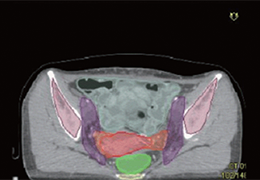

ART-Plan™ Artificial Intelligence Contouring